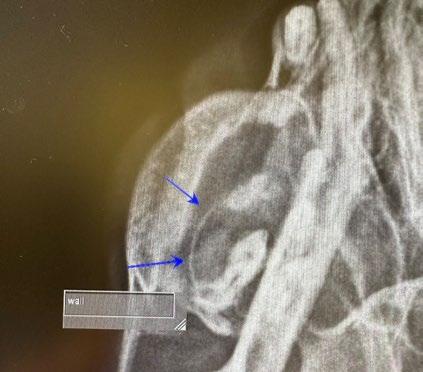

An 8-month-old female desexed Labrador retriever cross presented for a 4–6-week duration of left forelimb lameness.

On clinical exam, there was mild pain on manipulation of both shoulder joints.

Q. What is your radiological diagnosis?